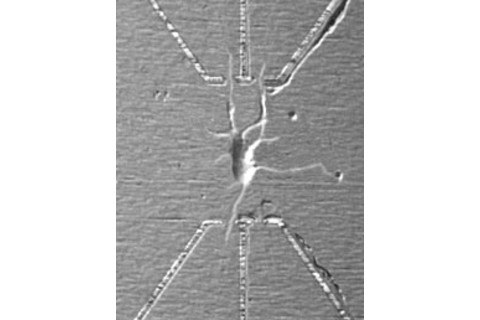

83 Nano Electrode Wires Neurons

In August researchers announced the creation of a microscopic device that can make an electrical connection to an individual neuron, an invention that might one day lead to synthetic substitutes for damaged nerve cells.

Charles Lieber, a chemist at Harvard University, and his colleagues devised a tool that can record, stimulate, and modulate signals at multiple points on a neuron, from individual dendrites to axons, essentially duplicating the way that brain cells communicate. The device is so small—just 20 nanometers across—that 50 can fit on a neuron. While other researchers have made electrical connections to the nervous systems of animals and humans, until now no one has been able to forge a link at the level of individual axons or dendrites. "These devices can be used not only to record signals but to apply voltages back to the nerve cell," Lieber says. "We could stimulate a neuron to fire and control the rate of propagation of the electrical impulse."

The invention has profound implications for research and treatment. Using multiple inputs, it could soon be possible to decipher how neurons pass signals back and forth and how learning, memory, and other processes occur. Implanted in the brain, Lieber's electrodes might one day serve as prostheses to help damaged nerves regain their function. "The goal," he says, "is the betterment of the human condition."